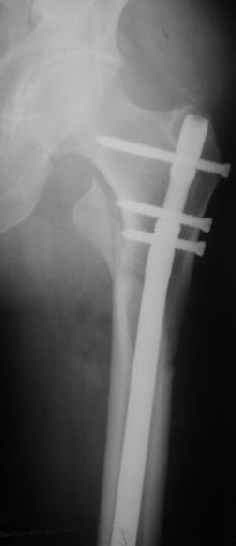

Картинка красивая, но на мой взгляд, не совсем оптимальная: Слишком медиально введён стержень - риск аваскулярного некроза головки бедра.

вариант межфрагментарного шинирования - зона достаточно простительная т.е. чрезвертельные переломы потенциально хорошо срастаются при любом

расположении сопредельных отломков- хорошая локальная васкуляризация. В приведённом случае я бы предпочёл принцип межфрагментарной компрессии (рекон/гамма нэйл 130- 135) принципу шинирования перелома.

Женя, эта картинка показывает не оптимальное лечение вертельных переломов в моем представлении, а особенности дизайна упомяутого фиксатора.

В частности, его возможности при фиксации переломов проксимального отдела бедра - в сравнении с другими, имеюшими лишь по одному статическому и динамическому отверстию и с кондуктором для введения 2 винтов.

Это было года 2,5 назад, мы тогда еще уточняли возможности шинирования с угловой стабильностью гвоздем с поперечным расположением винтов при переломах проксимального отдела бедра. Пациенту не пришлось приобретать намного более дорогой рекон или проксимальный гвоздь. В приложении еще несколько примеров применения того гвоздя при высоких переломах бедра, в том числе с более латеральной точкой входа. Гвоздь изгибаем для этого.